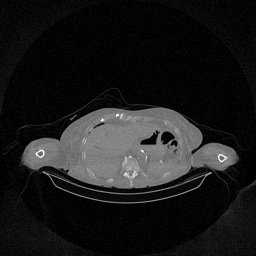

The results for simulated noisy data are shown in Fig. 2. The first and third rows display two representative slices from the test set, and the second and fourth rows present the corresponding error maps. The traditional WCE method suppresses cupping artifacts and recovers some missing anatomical structures but still shows noticeable deviations from the ground truth. Predictions from the four diffusion-based models demonstrate a markedly improved ability to restore anatomical structures. Among them, cDDPM fails to fully reconstruct the patient bed and retains residual noise in its outputs. This noise is attributable to an incomplete reverse denoising process rather than residual Poisson noise, as evidenced in our noise-free experiments (Fig. 5 in the Appendix). PatchDiffusion, diffusionGAN, and I2SB achieve similar visual quality, with I2SB producing the cleanest and most consistent reconstructions.

Quantitative results in Tab. V further confirm I2SB’s superiority over conventional deep learning methods such as FBPConvNet and Pix2pixGAN across RMSE, PSNR, and SSIM. Compared to other diffusion models—including cDDPM, PatchDiffusion, and cLDM—I2SB delivers higher image quality, while diffusionGAN achieves comparable quantitative performance. However, I2SB demonstrates a significant advantage in inference efficiency, as summarized in Tab. IV.